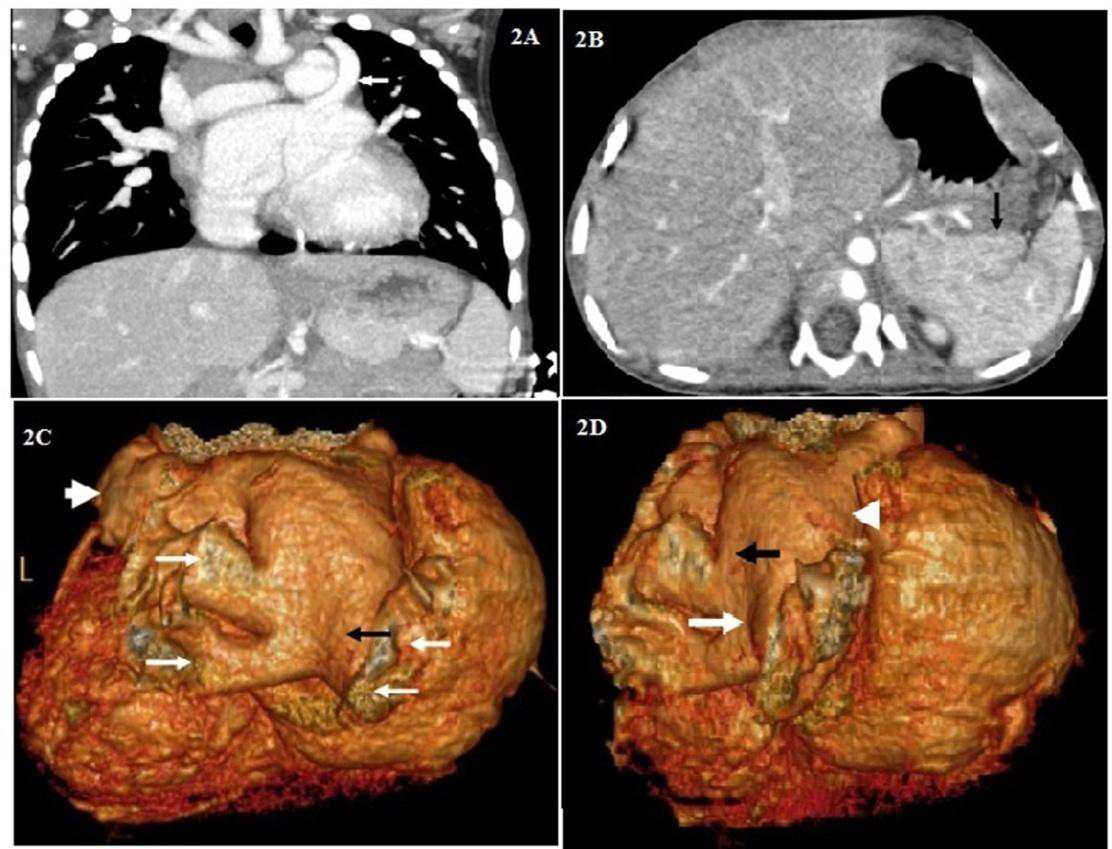

Further, in view of complex cardiac anomalies CT angiography was performed. Multi detector computed tomography (MDCT) study depicted a thick membrane (Figure 1A-1E) in left atrium with its compartmentalization. Aortic coarctation, membranous VSD, PDA, persistent left SVC (draining into coronary sinus) were well demonstrated. Two normal papillary muscles were seen. In addition polysplenia (Figure 2A- 2D) was seen in the absence of signs of heterotaxy syndrome. Based on the above findings diagnosis of cor triatriatum sinister was concluded.

The basic classification of cor triatriatum was framed by Loefller in 1949 [5] .The defect is classified into three types based on the anatomical feature of the defect like number and size of fenestrations in the fibromuscular membrane dividing the left atrium. Type 1: Defect having no opening, Type 2: Defect having one or more small openings and Type 3: Defect having single, large opening [5]. Apart from the Loefller classification the other reported forms of Cor triatriatum were based on the fenestration shape [6] and presence of Atrial Septal Defect (ASD) [7]. Cor triatratum sinister in paediatrics is commonly associated with congenital cardiac lesions like ostium secundum atrial septal defect and anomalous pulmonary vein return [8]. Our case is associated with VSD, persistent left SVC, PDA, polyspenia.

Since the end of the 20th century, echocardiography has been the mainstay of imaging for the diagnosis of cor triatriatum [9,10]. The echocardiogram includes study of the 2D pattern of the membrane, analysis of turbulent flow on color Doppler and determination of any gradient across the membrane on continuous wave Doppler. Furthermore, the existence of co morbid congenital cardiac anomalies can be studied by echocardiography. A retrospective review study showed that transthoracic echocardiography has 98% accuracy in diagnosis cor triatriatum [11].Currently, advanced sophisticated imaging techniques like cardiac CT have been extensively employed for the non invasive evaluation of coronary artery disease. Mounting clinical evidences report the diagnosis of cor triatriatum using CT [12,13]. Our case is unique in that it is the first report of 64- slice multi detector computed angiography revealing cor triatriatum with least common associations of PDA, VSD and polysplenia. Studies reveal that cardiac CT has potential benefits with safety and economical aspects when compared to the conventional coronary angiography in the non-invasive evaluation of coronary artery disease [14]. In addition, high spatial and temporal resolutions images in cardiac CT provide information regarding cardiac anatomy, wall motion and myocardial perfusion. In this regard, our case demonstrates the utility of CT in diagnosing the underlying complex anatomic abnormalities in cor triatriatum.